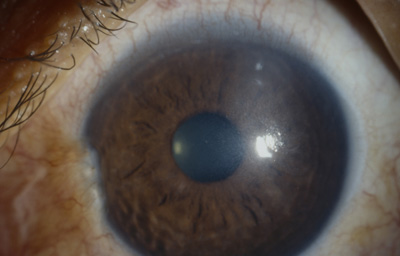

Al examen: Nubécula adelgazada “con aguijón desnaturalizado en córnea”; córnea sin edema con buena trasparencia y cámara anterior media. Iris con pupila negra, central y redonda con sinequia anterior de hoja anterior del Iris de 5 a 8 en periferia e Iridoschisis, sin pérdida de pigmento en el Iris . Cristalino trasparente, polo posterior bien. TO: 17 en ambos ojos aplanático de Goldman. (Fotos 26 y 27)

Foto 26 - Leucoma a las 2 con agujón “in situ

Foto 27 - Aguijón desnaturalizado